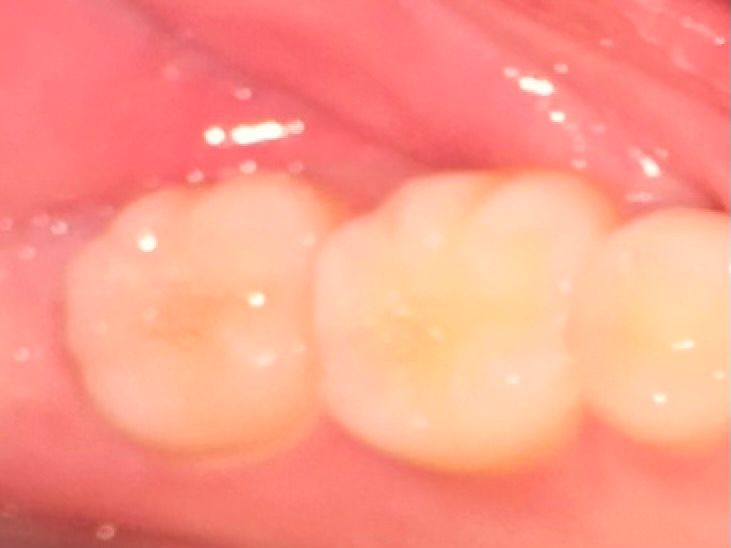

저기 맨 뒤 이빨입니다. 저번에도 이런적이 있어서 치과를 갔는데 충치는 없다고 하더라구요. 반년이상이 지나고 최근들어 또 뭔가 미세하게 시린 느낌이 나서,, 신경도 쓰여서 괜히 아픈 느낌이 들고 충치 맞나요? 맞으면 초기 인가요? 충치치료 아플까요?

사진에 보이는 부분에 잇몸이 안좋은거 같습니다. 일단은 잇몸치료를 먼저 받아보시는게 좋을것같습니다.

사진 상으로는 충치가 의심되지는 않습니다. 시린 증상 지속시엔 치과에서 검사 받아보시는 게 좋겠습니다.

사진으로만 봤을경우 크게 문제가 있는것으로 보이지는 않습니다 이런경우 치아에 너무 강한힘이 가해지는 것일 수도 있으니 치아에 가해지는 힘을 줄여주는 것이 좋습니다

외견상 충치은 없어보이고 단지 치태및 치석이 다소 끼어있으니 치과가서 스케일링 한번 받으시기 바랍니다